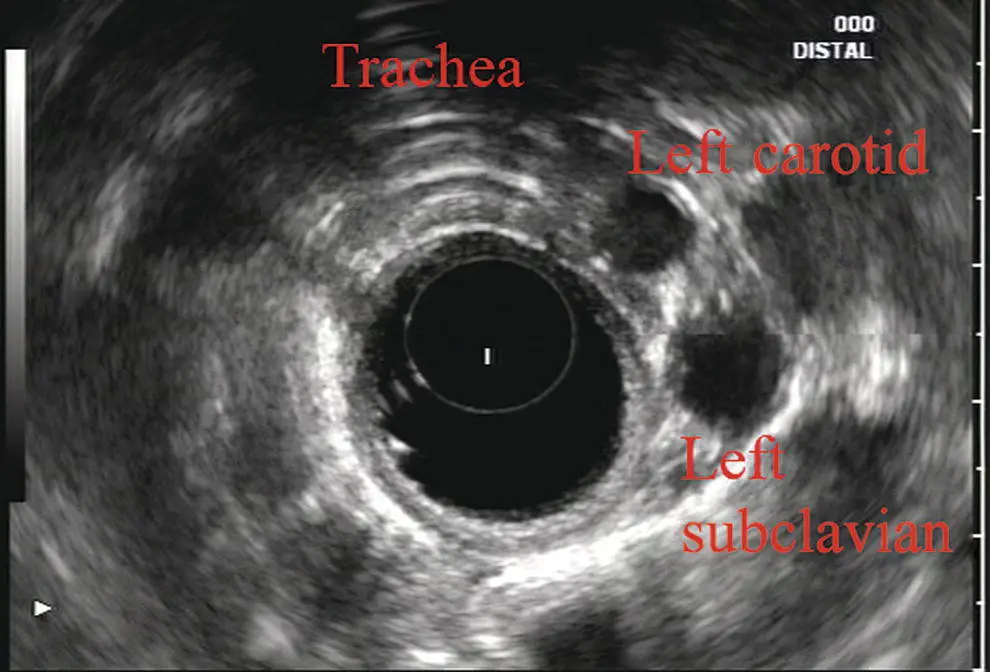

More proximally from the area at the AP window the aorta elongates and forms the aortic arch ( Figure 2.7). This usually creates a semicircle on the entire right side of the image correlating to the left‐sided arch. However, with usual orientation the aorta should not cross the midline. The left carotid and left subclavian artery can easily be seen to leave the aortic arch as small round structures on the right side of the image ( Figure 2.8). The brachiocephalic artery can sometimes be seen as well superior to the carotid on the right. As the scope is withdrawn the thyroid comes into view. For example, on the right of Figure 2.9a prominent thyroid can be seen with a cystic structure within it.

Figure 2.8 Radial array image at the level of the left carotid and subclavian arteries.